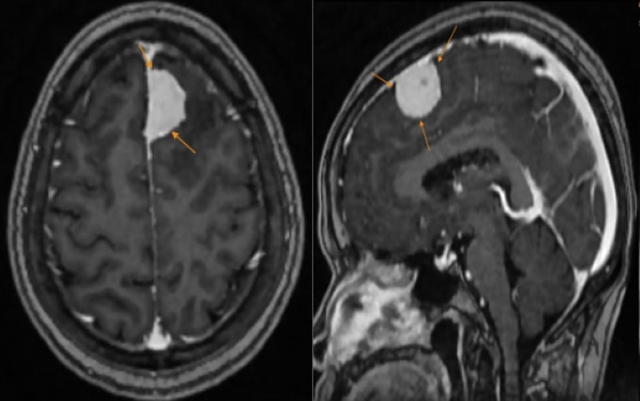

Hình ảnh khối u được phát hiện trên phim chụp MRI. Ảnh: BVCC

Tại đây, kết quả thăm khiến cô H. vô cùng bất ngờ: hình ảnh MRI ghi nhận có một khối u lớn vùng trán trái kích thước khoảng 27x15mm, nghĩ nhiều đến u màng não. Các bác sĩ đã đưa ra tư vấn định hướng phương án can thiệp kịp thời.